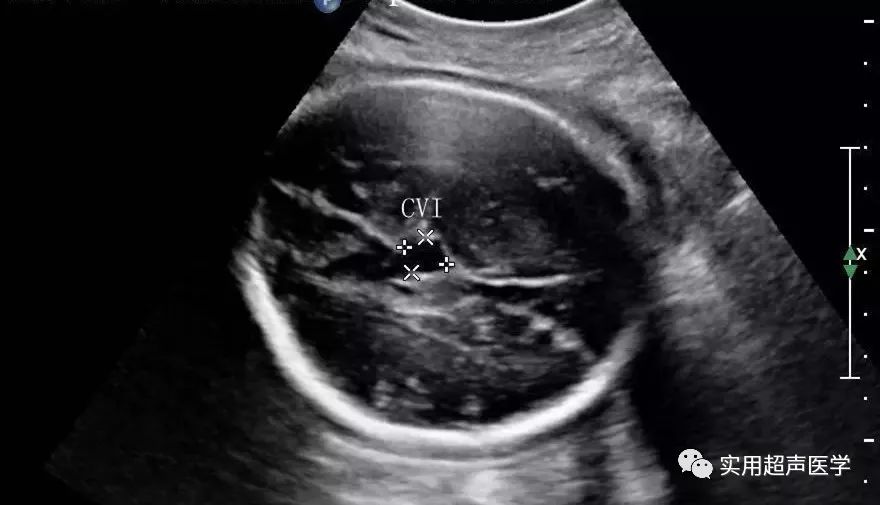

中间帆腔(CVI ),又称脑室间腔或者为帆间池,由中间帆池扩张而成,位于韦氏腔(CV)下方,第三脑室的上方,由穹隆脚间开始,两侧为丘脑,向后与四叠体池相通。

中间帆腔测量的标准切面为丘脑平面,此腔与透明隔腔及韦氏腔一样均不参与脑脊液的循环,为潜在的腔隙,此腔位于韦氏腔下方,第三脑室的上方,此腔向后经胼胝体下方可通大脑大静脉池。